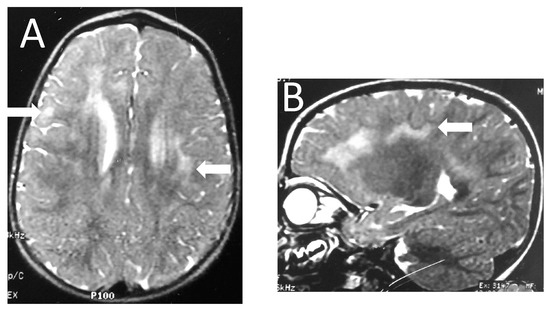

| Image Modality | Patient | 1 | 2 | 3 | 4 | 5 | 6 |

|---|---|---|---|---|---|---|---|

| Distribution | Diffuse/homogeneous | Patchy/asymmetric | Patchy/asymmetric | Patchy/asymmetric | Patchy/asymmetric | Patchy/asymmetric | |

| MRI at onset | Predominant location | Diffuse | Frontal and anterior temporal | Frontal and anterior temporal | Frontal and anterior temporal | Frontal and anterior temporal | Frontal and parietal |

| Infratentorial involvement | Pons | - | - | - | - | Pons | |

| Contrast enhancement | + | - | - | - | - | - | |

| MRI at follow up | Months after onset | 1st episode 8 mo (2 y 3 mo old) | |||||

| 2nd episode | |||||||

| 12 mo | 4 y | 10 mo | 24 mo | 13 y | 5 mo | ||

| (6 years old) | (6 years old) | (2 y 2 mo old) | (3 y 2 mo old) | (13 years old) | (20 mo old) | ||

| WM lesions improvement | Marked | Marked | Marked | Marked | Marked | Marked | |

| Brain Atrophy | Mild | - | Mild | - | - | - | |

| CT scan | Time after onset | 5 y | 4 y | 7 y | 1 mo | 13 y | 2 mo |

| Calcification | - | - | - | Basal ganglia | - | - |